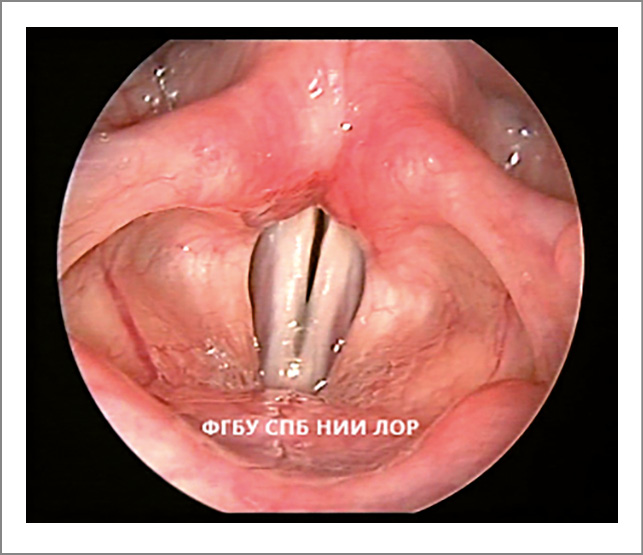

- Недостаточное натяжение медиального края голосовой складки во время вдоха обусловлено снижением тонуса голосовой (m. vocalis) и щитоперстневидной (m. anticus) мышц. Край выглядит несколько вогнутым (рис. 3).

- Симптом «зияния гортанных желудочков» характеризуется максимальным отведением вестибулярных складок при вдохе, что позволяет увидеть гортанные желудочки; следует отметить, что в здоровой гортани гортанные желудочки необозримы.

Рис. 3. Функциональная дисфония по гипотонусному типу (вдох): зияние гортанных желудочков, недостаточное натяжение медиального края голосовых складок.